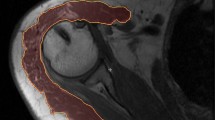

Subjects were seated with the affected (patients) or dominant (controls) arm fully suspended in a splint that was attached to a force sensor (AMTI-300, Advanced Mechanical Technology Inc., Wavertown, MA, USA). The two translational degrees of freedom perpendicular to the humerus were fixed, and the longitudinal translation and three rotational degrees of freedom were released (Fig. 1). The splint allowed for variation in point of force application (force sensor) alongside the humerus. In this way, external moment loading can be varied, without changing task force magnitude. Subjects were instructed to maintain the arm in a standardized position during the experiment: arm elevation of 60°, 30° of horizontal abduction with the humerus 45° internally rotated, as applied in previous studies with this setup [3, 4, 16, 23, 26, 27]. Arm position was visually controlled for by markings on the experimental setup. The arm was fully supported for gravity in this specific condition, so subjects were able to maintain the arm this way without any effort.